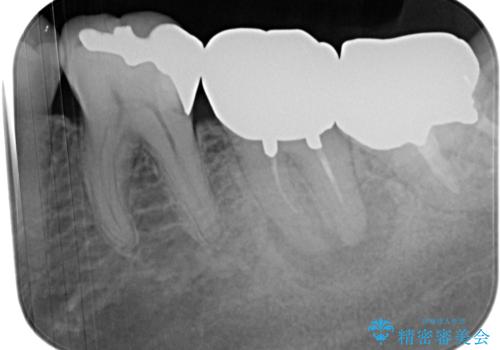

診察の結果、既に根管治療をされている第二大臼歯の根尖部に大きな病変があり、それが痛みの原因であるため、根管治療が必要と判断されました。

根管治療後6か月が経過してレントゲンを撮影したところ、非常に大きかった病変が小さくなっていることが確認されました。